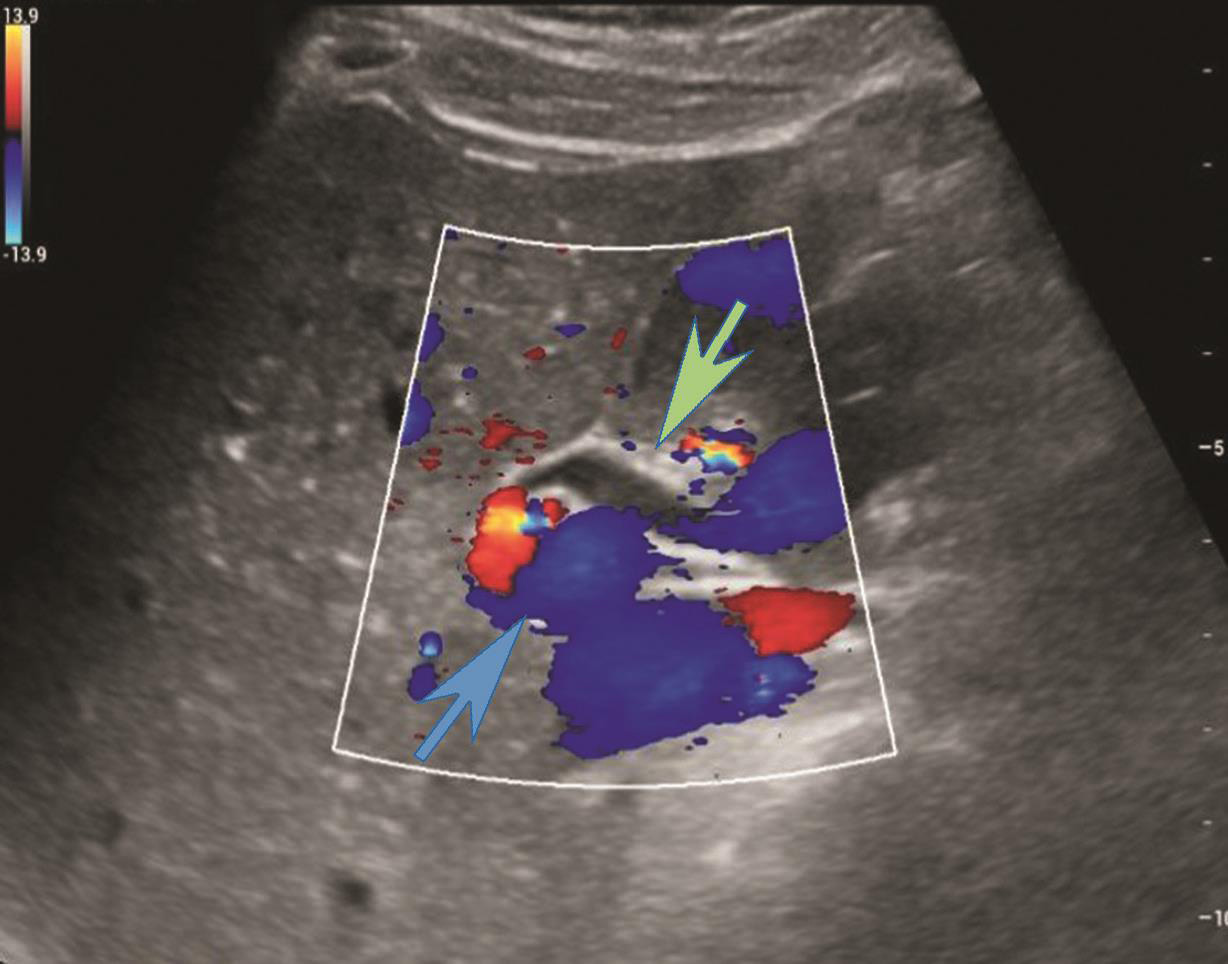

(4)肝门部肝外胆管上段灰阶超声图像及CDFI图像(图2-1-2,图2-1-3)。

图2-1-3 肝门部肝外胆管上段CDFI图像

肝外胆管(绿色箭头)内未见血流信号充盈,后方门脉主干内可见蓝色血流信号充盈(蓝色箭头)